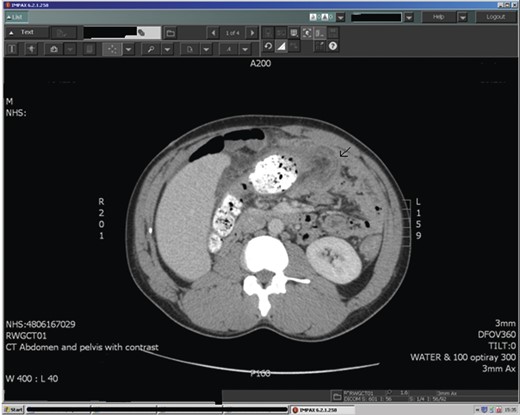

Abdominal ultrasound demonstrated a bowel-related mass lesion in the epigastric region (Fig. 1). Computed tomography (CT) scan of the abdomen and pelvis revealed a 3 × 6 cm fatty ovoid lesion within the transverse colon resulting in intussusception (Fig. 2). Colonoscopy showed an abnormal dusky grey lesion occupying most of the lumen in the distal transverse colon. There were two ulcerated areas on the front of the lesion, most likely the leading point of the intussusception. A laparotomy was performed. Intussusception of the transverse colon was found, for which an extended right hemicolectomy was performed (Fig. 3), with ileo-transverse colon anastomosis and defunctioning loop ileostomy. The patient had an uneventful postoperative recovery and returned later for reversal of his loop ileostomy. The histopathology report confirmed a 6 × 4.5 cm submucosal lipoma acting as a leading point for the intussusception. There was no evidence of malignancy.

Abdominal CT is considered the most sensitive radiological method for diagnosis of intussusception, with characteristic features of a ‘target’ or ‘sausage’ shaped soft tissue mass with a layering effect [7]. Identification of a lead mass is often possible, although determining the underlying aetiology is difficult. On a CT scan, a lipoma manifests as a well-marginated spherical or ovoid mass, with fat attenuation.